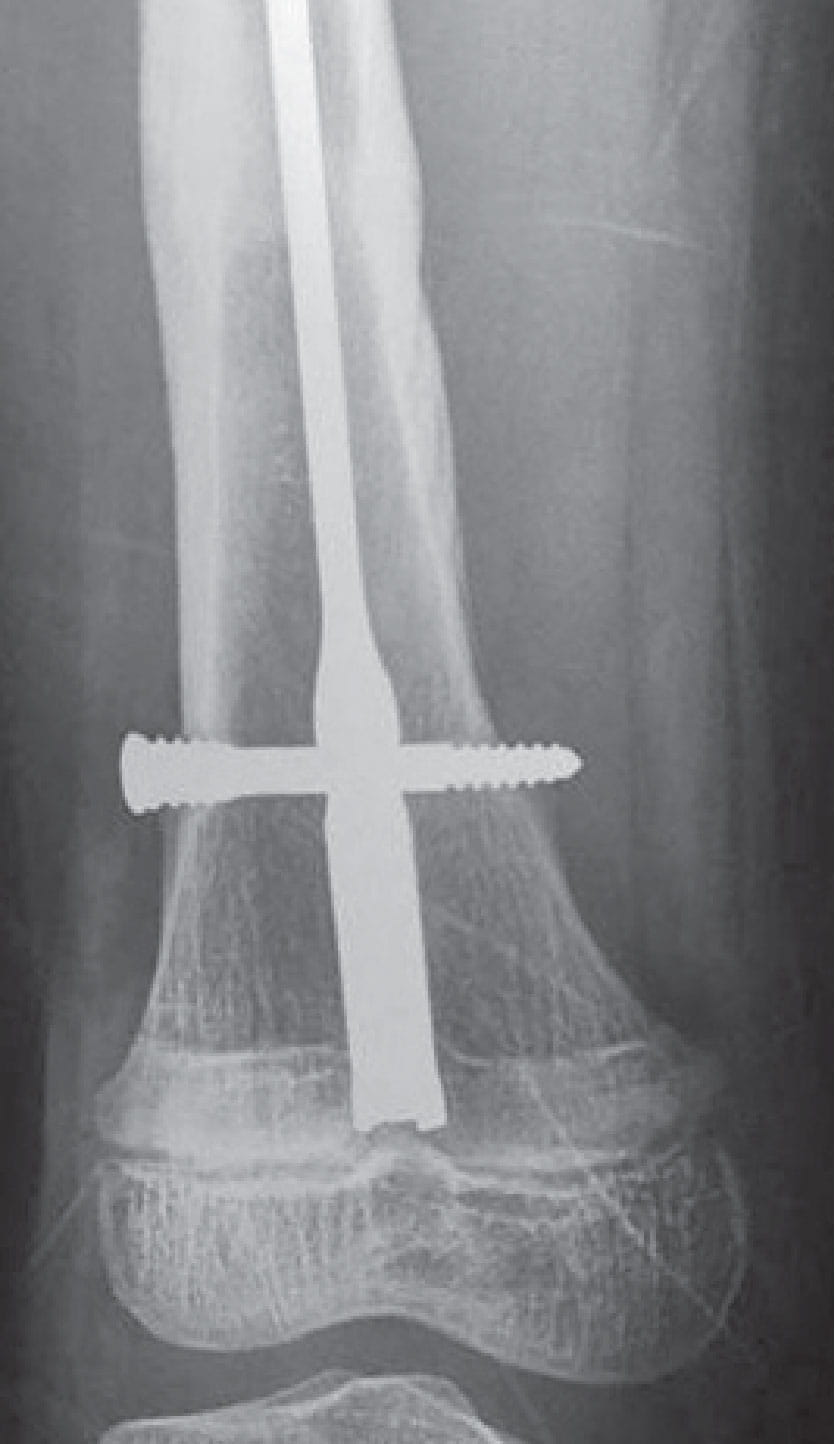

Ortho fracture repair figure 1AFigure 1A: This 11-year-old boy was treated in Mongolia with a retrograde femoral nailing for his distal femoral shaft fracture.

Ortho fracture 1BFigure 1B: Nine months later, radiographs demonstrate appropriate growth of the distal femoral with change in position of the nail versus the growth plate and a bony line called a Harris growth arrest line, which supports that the bone is growing reasonably.